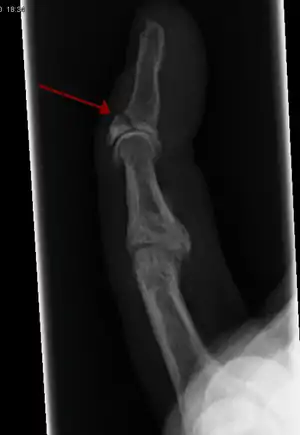

| Photo | Type | Description | Causes | Effects |

|---|---|---|---|---|

![]() In the fingertip. More images |

Linear fracture | Parallel to the bone's long axis | ||